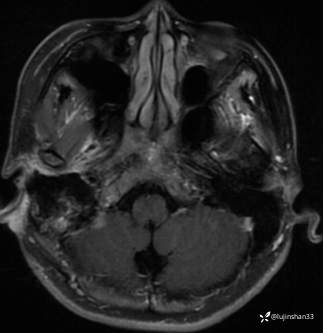

颞骨MRI: